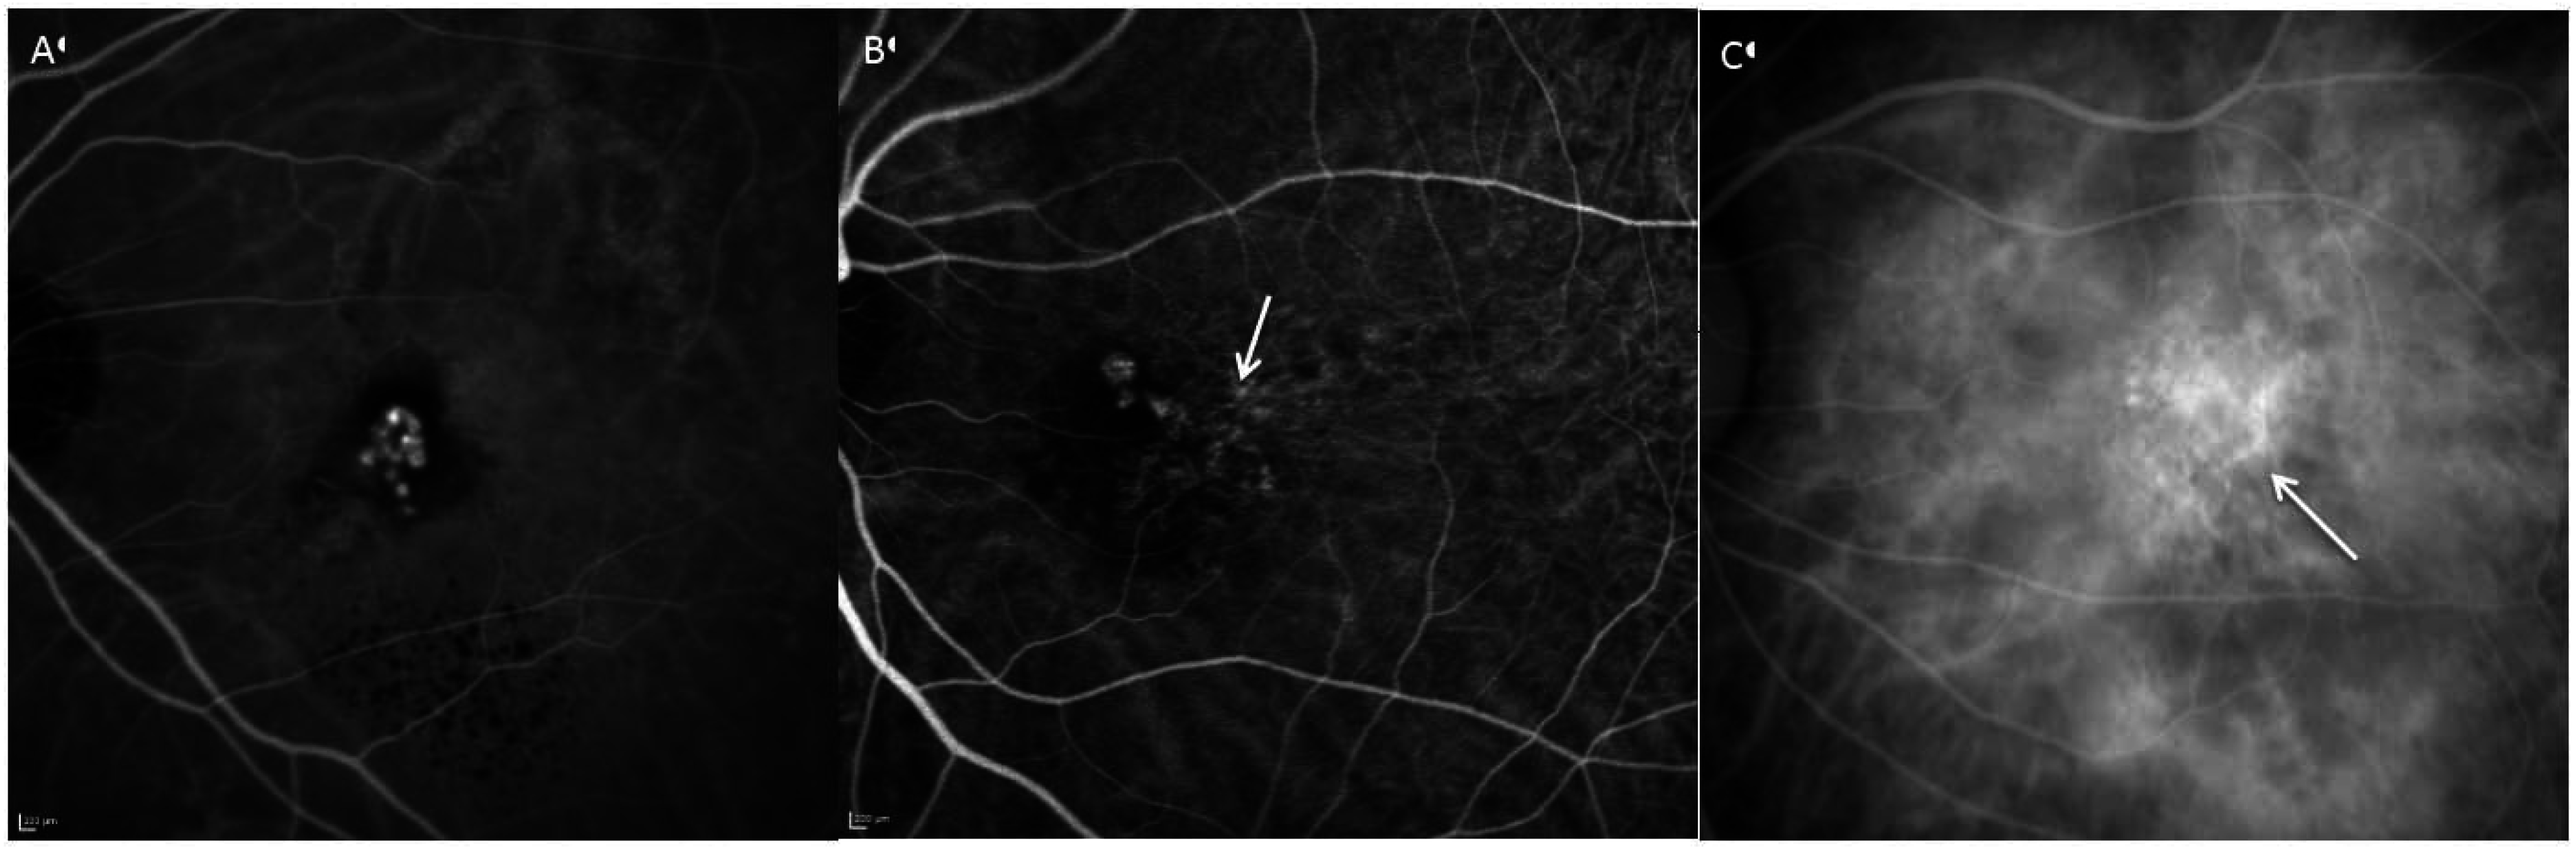

Figure 2.

Angiographic patterns of PCV: Cluster of grapes configuration (A), solitary (B) and string of pearls (C). Branching vascular networks (white arrow) are seen in figure B and C.